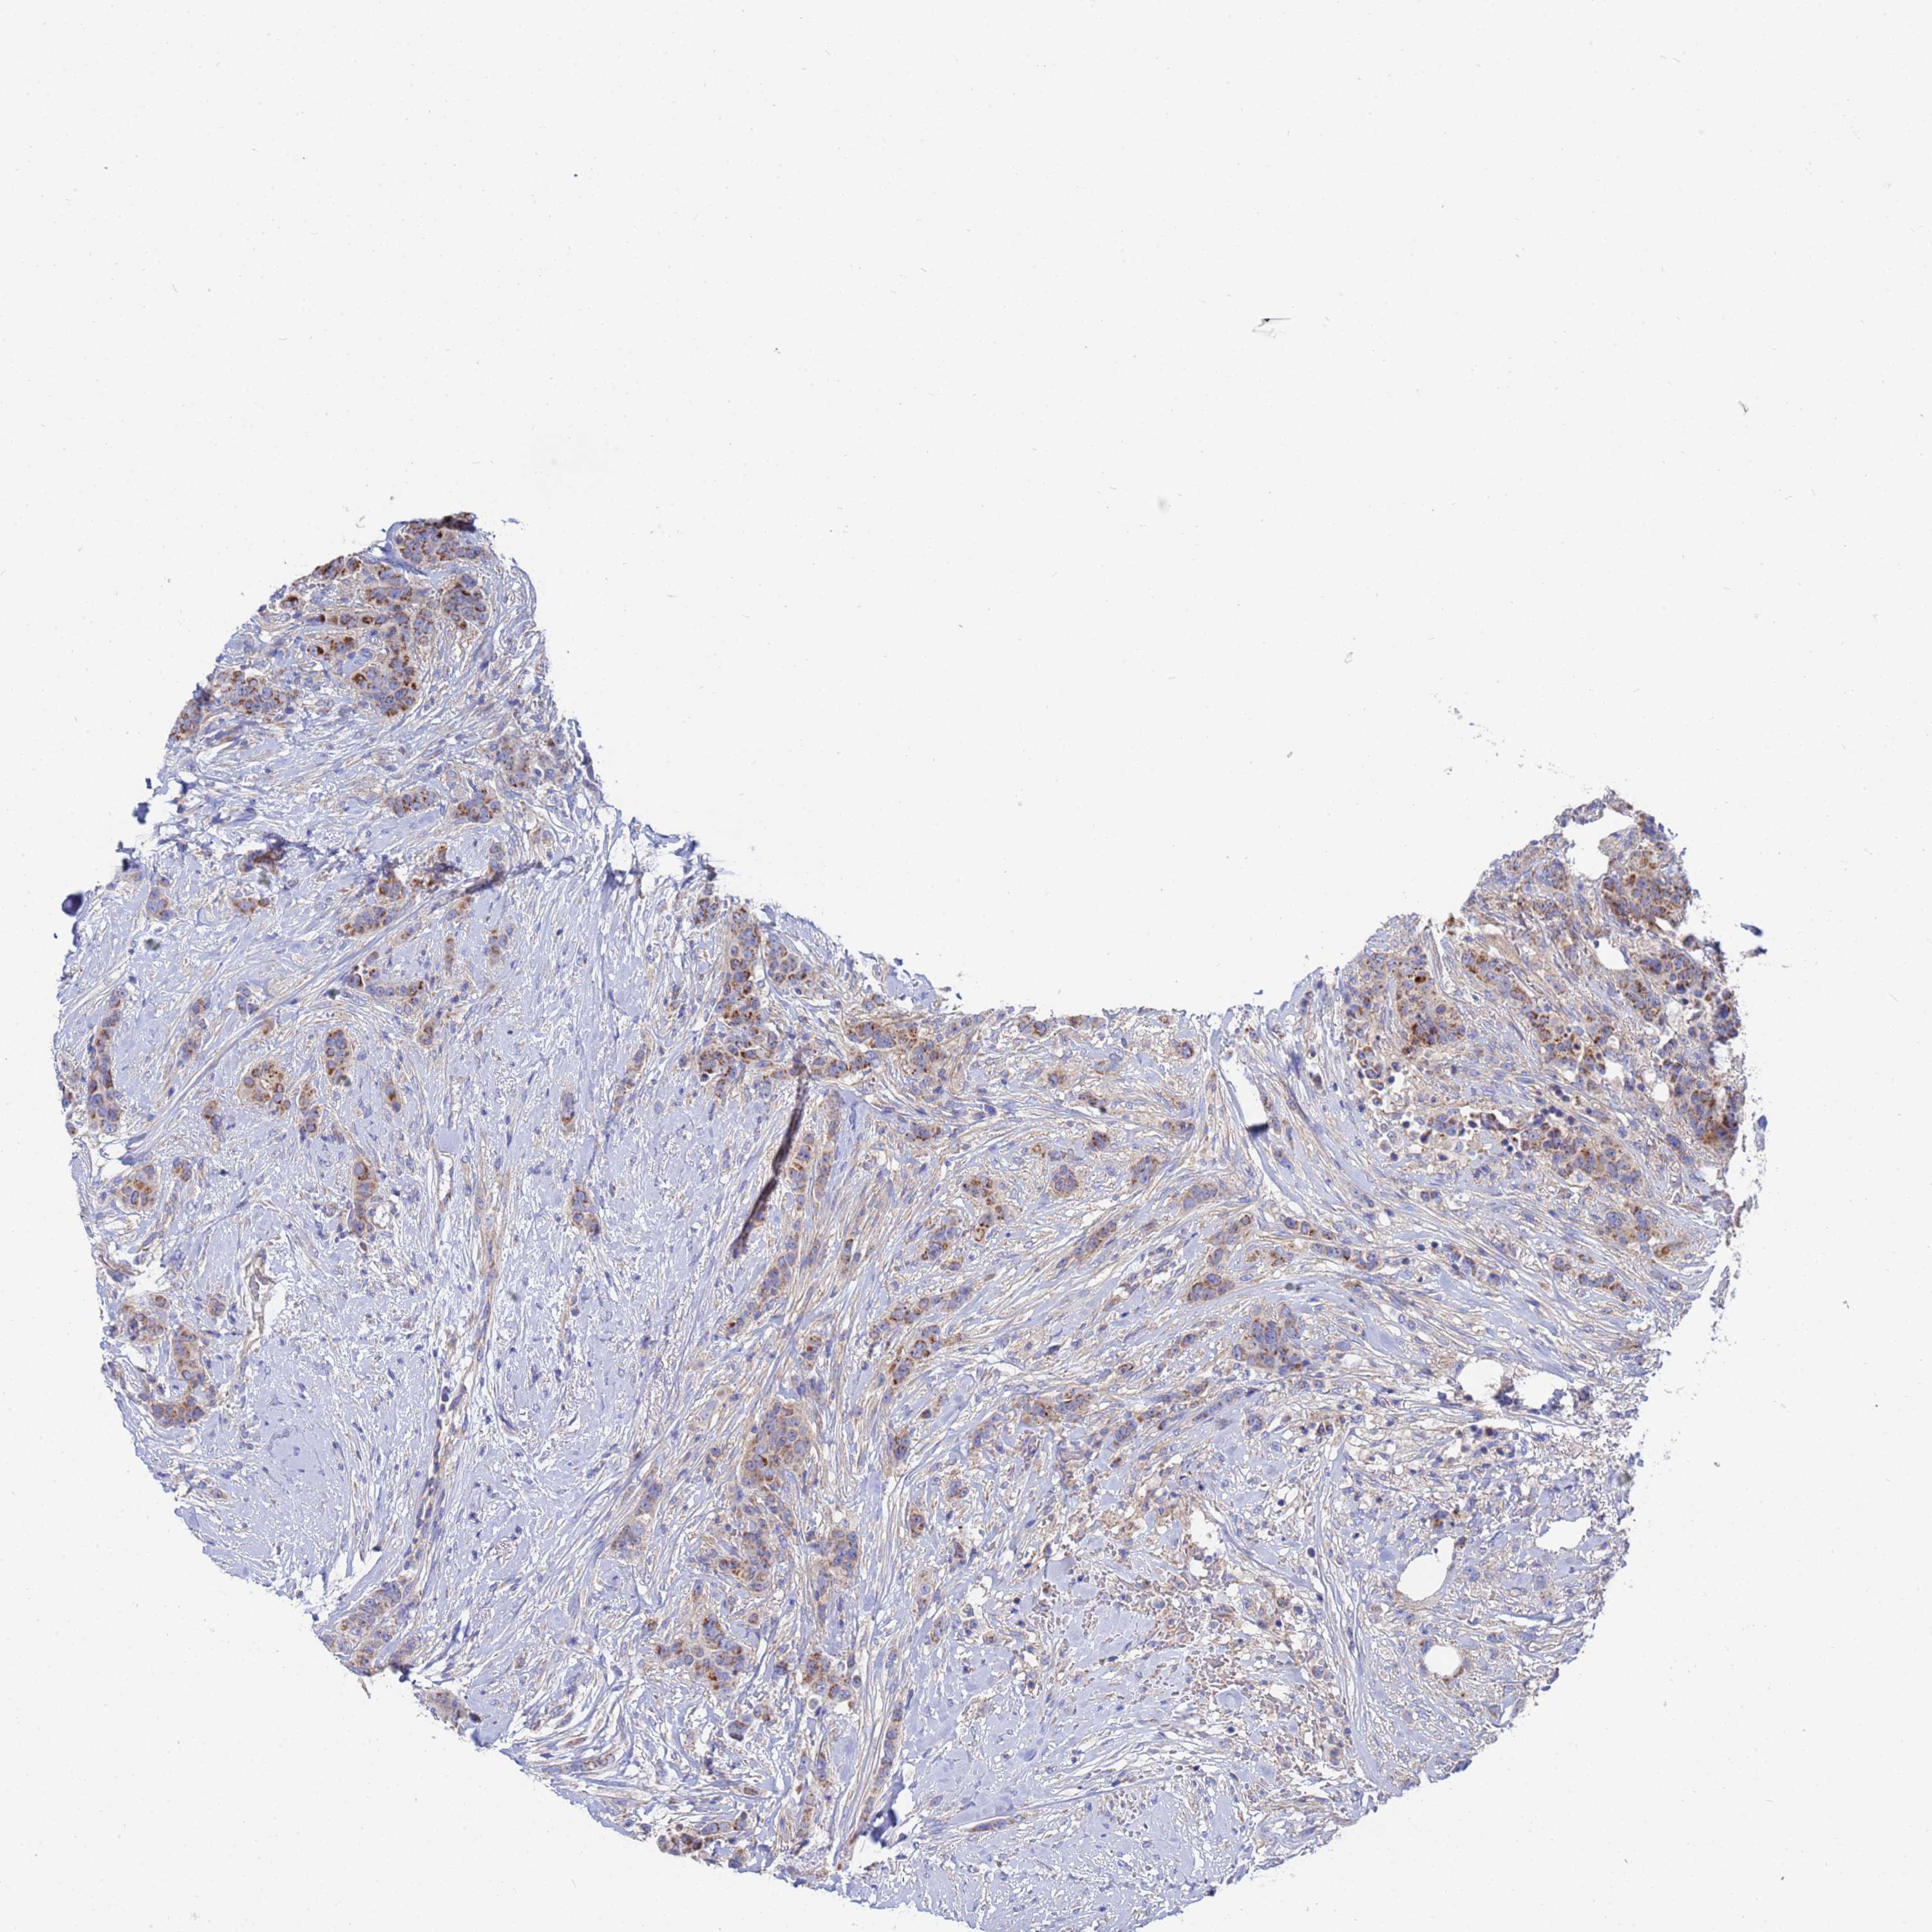

CANCER BREAST CANCER Show tissue menu

BRCA TCGA BRCA VALIDATION PROTEIN EXPRESSION